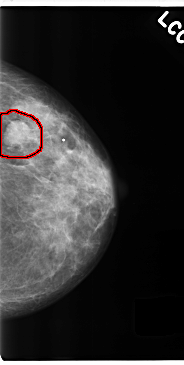

C_0212_1.LEFT_CC

FILE: C_0212_1.LEFT_CC.OVERLAY

TOTAL_ABNORMALITIES 1

ABNORMALITY 1

LESION_TYPE MASS SHAPE OVAL MARGINS CIRCUMSCRIBED

ASSESSMENT 4

SUBTLETY 5

PATHOLOGY MALIGNANT

TOTAL_OUTLINES 1

BOUNDARY